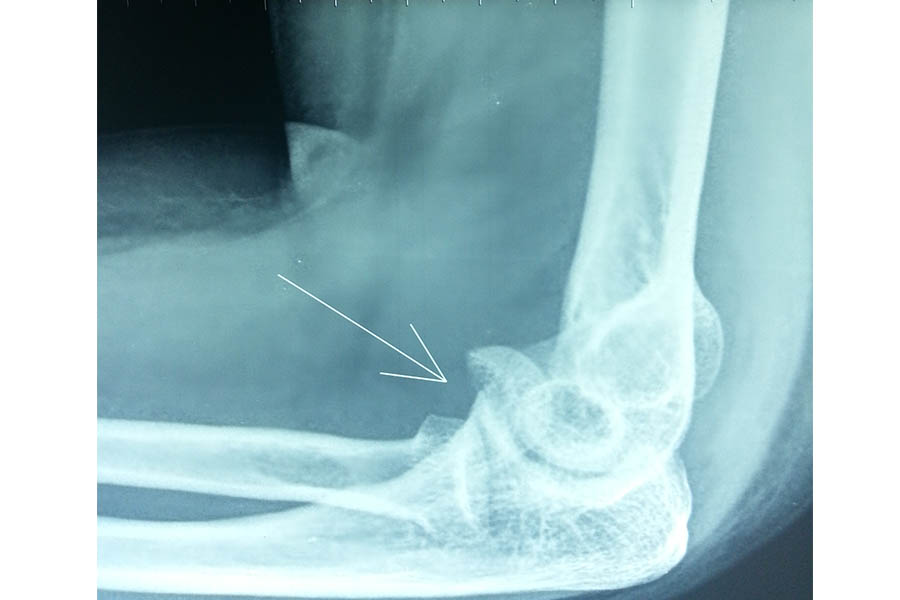

Trauma

Case 1